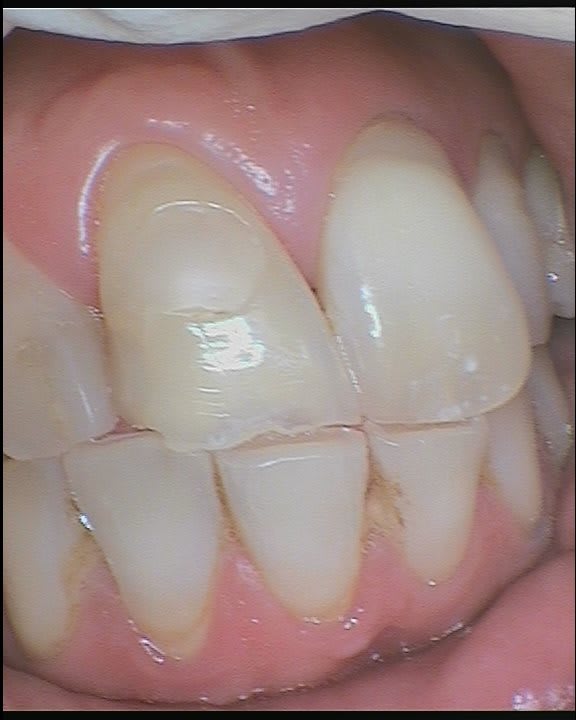

Ci joint une photo de mon patient qui souhaiterait restaurer son incisive, usée (pourquoi depuis combien de temps il ne sait pas), en position de propulsion quasi maximale.

Le problème est qu'en propulsion, incisive centrale supérieure et inférieure se font guide. Si je colle un composite dans cette situation, ça risque de ne pas aller.

En fait la dent n'est pas usée mais ébréchée ce qui pourrait signaler des micro chocs à repetitions et un probleme d'occlusion. Les autres dents adjacentes ne presentent pas la même altération . Il est possible que la mandibule soit en propulsion et frappe en priorité sur cette dent à la fermeture. Vérifie l'occlusion en propulsion et en lateralité. Propose lui de pour la dent legerement car si tu mets une obturation elle sautera et le fait de meubler la dent antagoniste ( à ne pas faire bien sur) ne changera rien si ce n'est ce n'est amener un probleme supplémentaire à savoir la création d'un décalage en marche d'escalier difficile à gérer par la suite.

Effectivement c'est une interférence postérieure, qui a amène à frapper sur la dent. Il manque la 46, et 47 48 sont très versées.